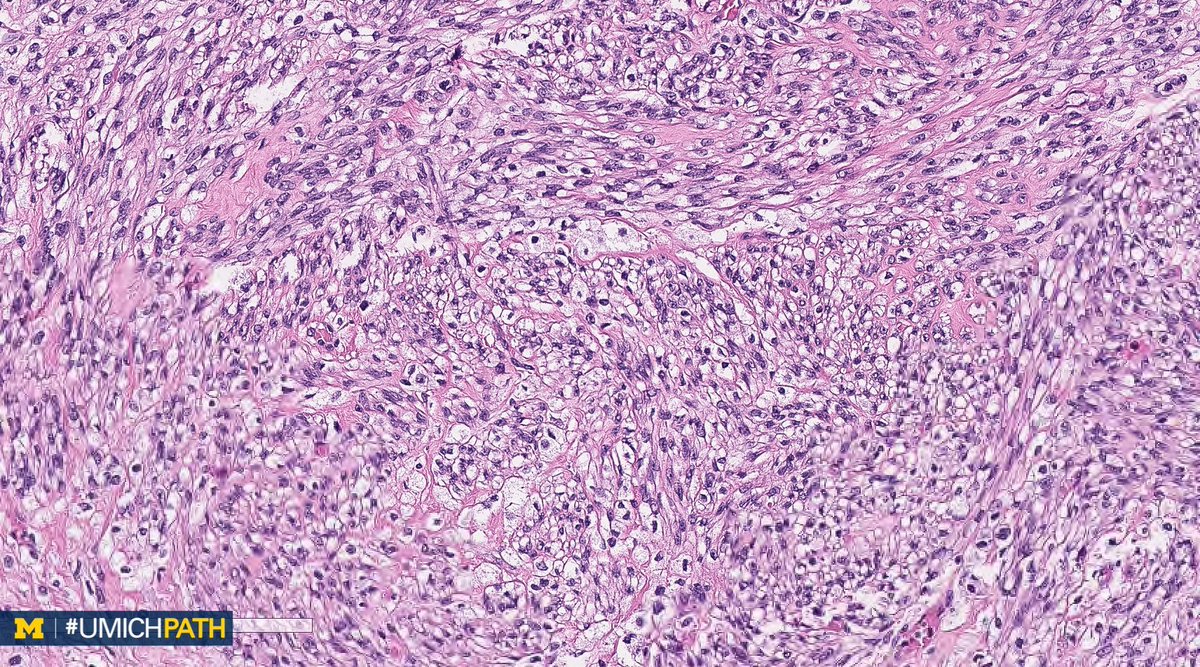

We're sharing 2 cases today since we missed #GYNPath Day 5 last week. What’s your #DailyDx of this uterine mass? We’ll tweet the answer and some quick facts tomorrow! #UMichPath

What’s your #DailyDx of this uterine mass?

We’ll tweet the answer and some quick facts tomorrow! #UMichPath

A: (Müllerian) adenosarcoma. Malignant stroma w/ associated benign epithelium (endometrioid or metaplastic); has “Phyllodes-like” architecture w/ stromal condensation. Can be low grade or have sarcomatous overgrowth (>25%) w/ high grade or heterologous sarcoma. #GYNPath #DailyDx

UMichPath's tweet image. A: (Müllerian) adenosarcoma. Malignant stroma w/ associated benign epithelium (endometrioid or metaplastic); has “Phyllodes-like” architecture w/ stromal condensation. Can be low grade or have sarcomatous overgrowth (>25%) w/ high grade or heterologous sarcoma. #GYNPath #DailyDx